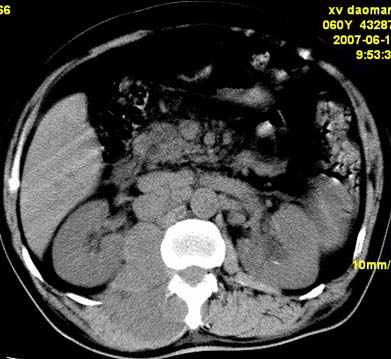

以下是引用刘明在2007-6-26 16:00:00的发言:[br][br]右侧竖直肌及腰大肌肿胀,脂肪间隙难辨,腹膜后血管旁见多个肿大淋巴结影,椎体附件右侧有压迫吸收、未见硬化迹象,考虑椎旁冷脓肿可能[br]左侧肾盂内可见高密度影,周围有毛刺,本图象是平扫,不是增强,应该是结石[br]

以下是引用hhcckk在2007-6-27 9:41:00的发言:[br]肾周筋膜增厚,胰腺影肥大,楼主是考我们了,我考虑是胰腺炎引起的腰部感染,形成的蓝棕色斑,也称gray-turner征,另外腹膜后怎么这么多的淋巴结,转移也要考虑[br]结核三个月没有骨破坏?寒性脓肿累及到竖脊肌的少见,所以我考虑结核的可能性不太大[br]左肾内高密度影,密度不太均匀,左肾有积水的表现,考虑是结石[br]期待楼主老师的结果